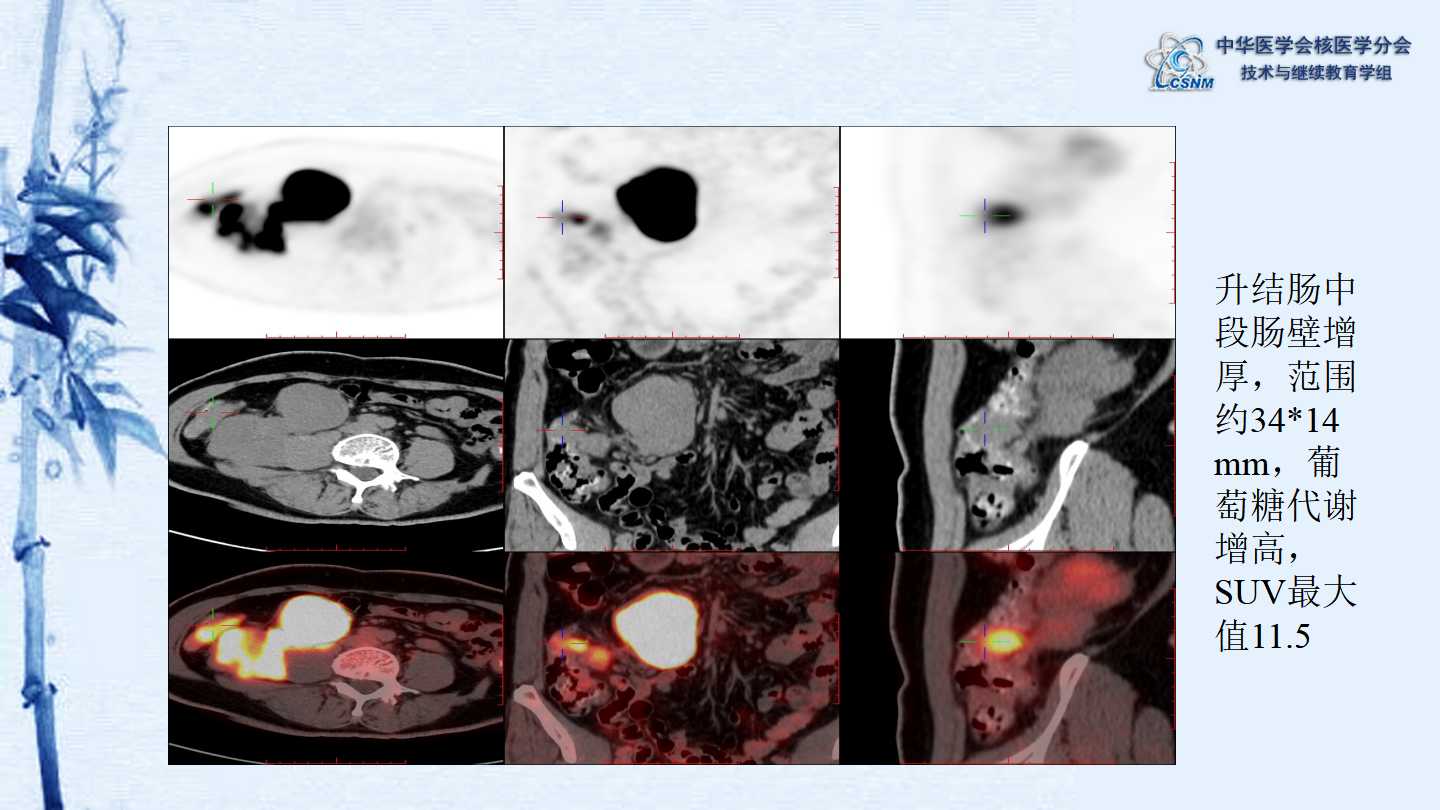

【CSNM继教学组】病例E51-邢岩-结肠炎性肌纤维母细胞瘤18F-FDG PET/CT显像